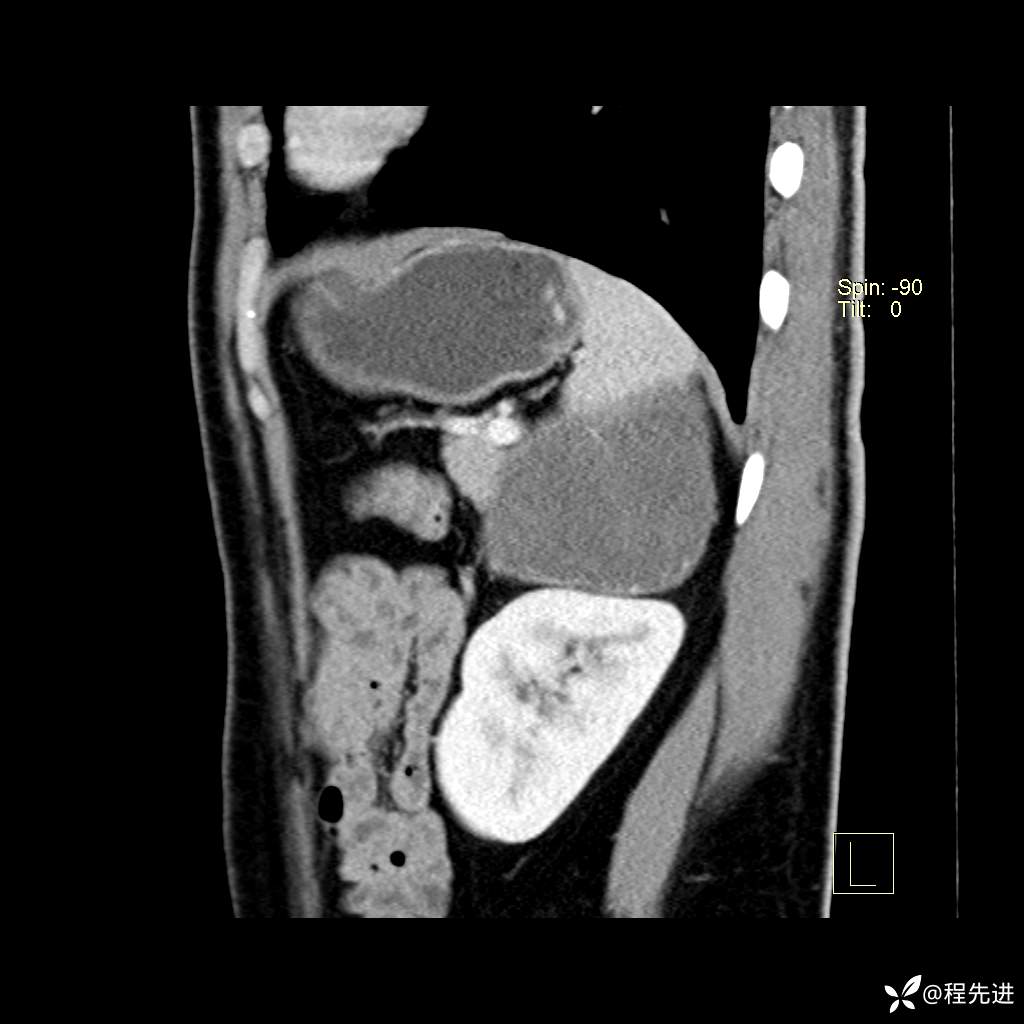

矢状位重建: